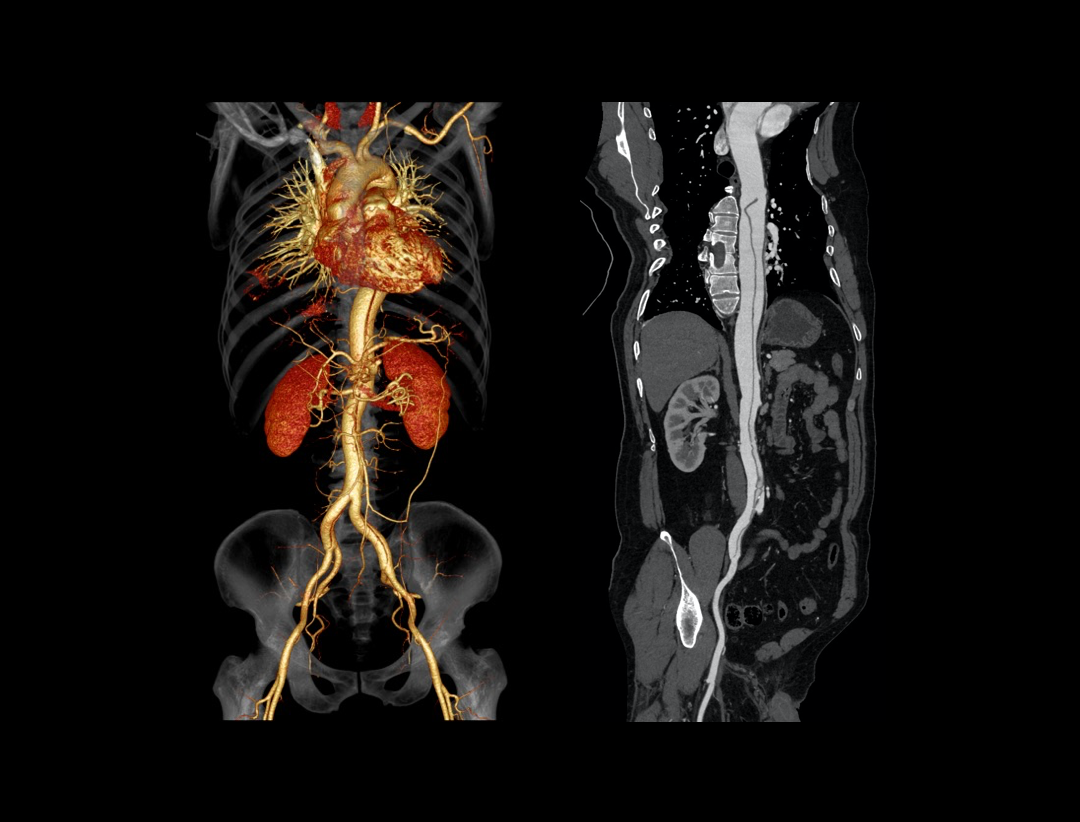

Aortic Dissection

Run-off CTA